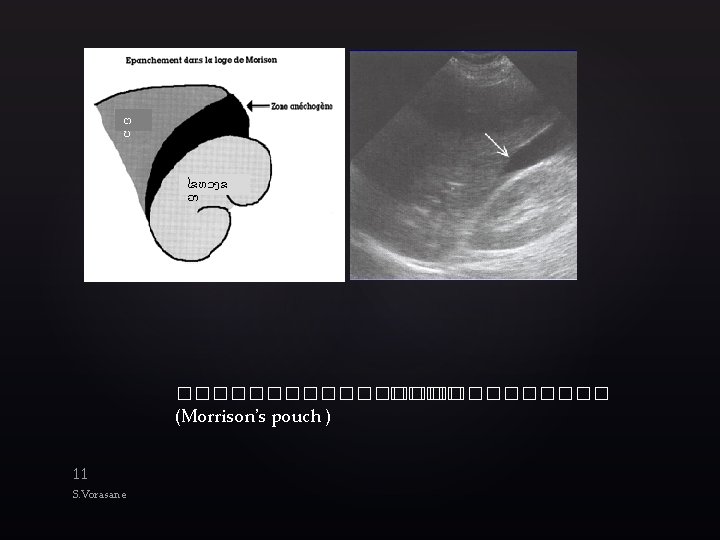

Technique l Goal: to identify blood in body cavities where it is not supposed

Technique l Goal: to identify blood in body cavities where it is not supposed to be l l Unclotted blood appears black on US Clotted blood appears gray Abdominal probe with small footprint (between 13 cm) with range of frequency between 2. 0 Hz and 5. 0 Hz Scan 4 areas l l RUQ Subxiphoid LUQ Suprapubic